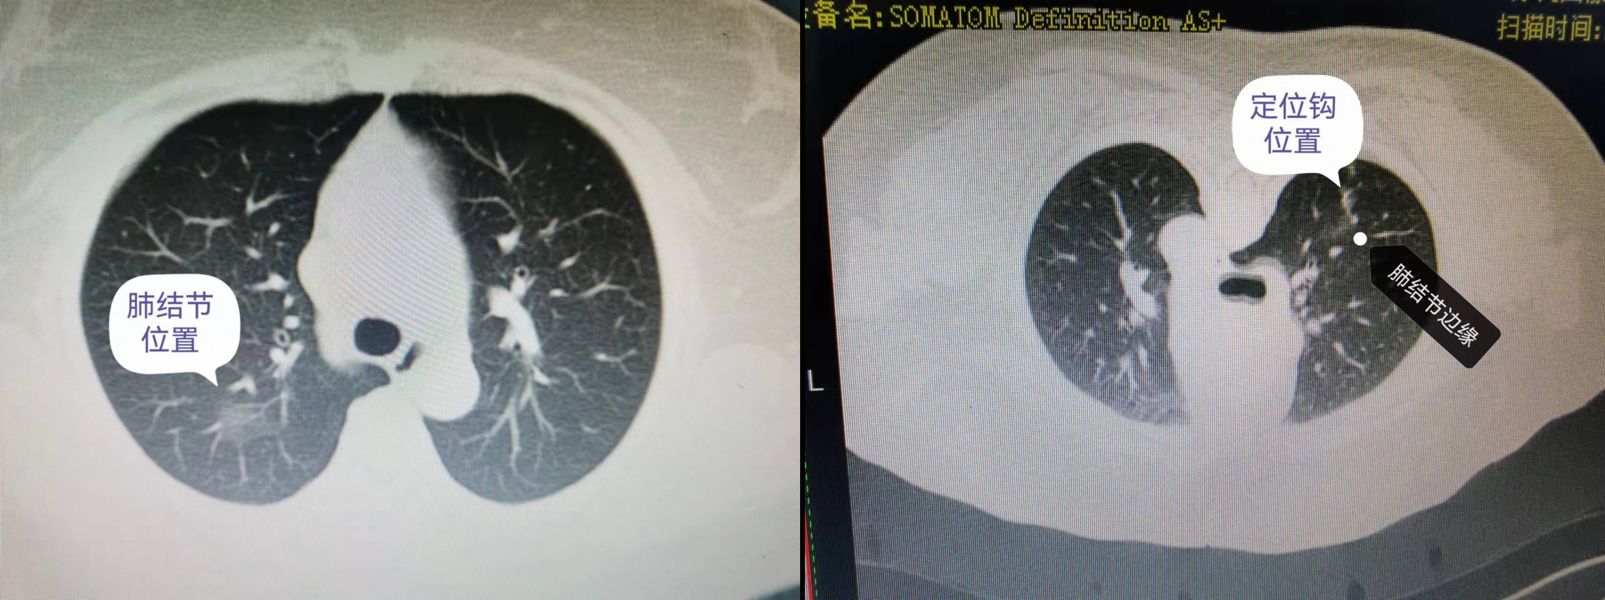

术前CT影像资料(肺结节)CT介导下定位后(俯卧位)

术前规划时,以科主任黄勇为首的心胸血管外科团队联合CT诊疗中心经积极讨论,并结合既往经验认为患者磨玻璃病变位于右上肺后段可施行解剖性肺段切除术,考虑其病变密度低,术中靠传统定位手段(手指触诊)难以准确定位,经研究讨论后决定实行术前CT介导下穿刺定位(以肺结节定位钩穿刺于结节旁为引导),术中精准判断病变位置后,经该科手术团队历经2小时的努力,顺利进行了胸腔镜下精准解剖性右上肺后段切除术,完整保留了右上肺尖、前段肺组织,手术过程顺利,出血甚微,患者术后恢复良好。